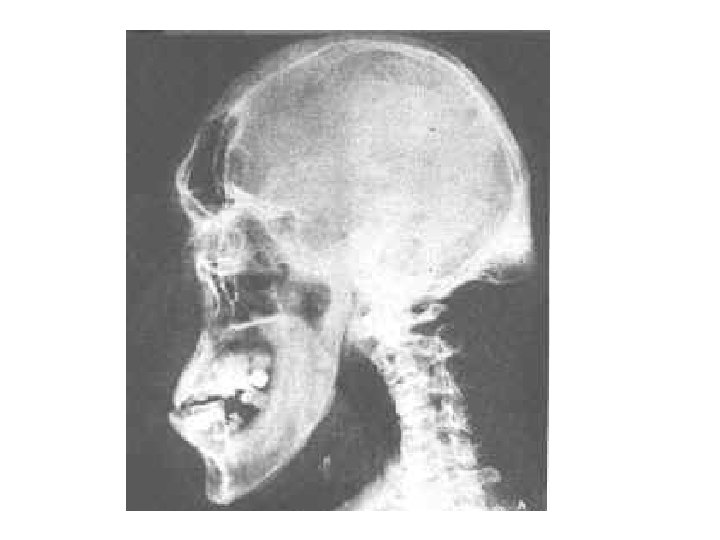

Acromegaly • Acromegaly is a serious condition that occurs when the body produces too much of the hormones that control growth. ・The hormone most often affected is called growth hormone, or GH. Itハis produced by the pituitary gland, a tiny organ at the base of the brain. ・・ Growth hormoneハpromotes growth of bone, cartilage, muscle, organs, and other tissues. ・・When there is too much growth hormone in the body, these tissues grow larger than normal. This excessive growth can cause serious disease and even premature death.

The Skull • 8 sutured bones in cranium • Facial bones: 13 sutured bones 1 mandible Cranium encases brain attachments for muscles sinuses